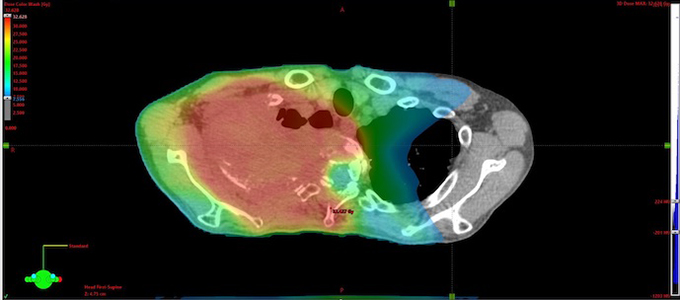

RALS Horizontal cross-section images

(3) Intensity modulated radiation therapy

High-precision radiotherapy is performed on the head and neck, lungs, and prostate, etc. of the body, organs according to the shape of the tumor and avoiding surrounding normal tissue.

Chest IMRT

Based on the CT images, the radiotherapist decides on the irradiation method, and calculations are performed by a 3D treatment planning system (Eclipse, iPLAN, etc.), and the data is sent to the treatment device.